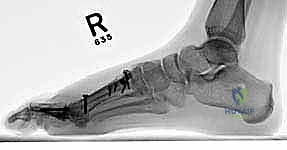

- الأشعة السينية مع تحمل الوزن (Weight-bearing X-rays): صور من الأمام، الجانب، والزوايا المائلة لتقييم زوايا العظام تحت تأثير وزن الجسم.

- تصوير السمسمانيات (Sesamoid view): لمعرفة ما إذا كانت العظام السمسمانية قد خُلعت من مكانها.

- الأشعة المقطعية (CT Scan): في الحالات المعقدة، يستخدم الدكتور هطيف الأشعة المقطعية ثلاثية الأبعاد لتقييم التئام العظام السابق، ومواقع المسامير القديمة، ودرجة خشونة المفاصل بدقة متناهية.

- يتم تحديد مواقع المسامير أو الشرائح المعدنية من الجراحة السابقة وإزالتها (Hardware Removal). قد تكون هذه الخطوة صعبة إذا نما العظم فوق المسامير.